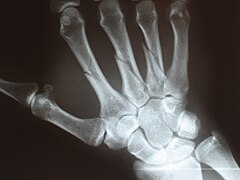

Ладьевидная кость — одна из так называемых запястных костей в районе запястья (рис. 1).Рис. 1

Диагностика: Иногда довольно сложно определить перелом ладьевидной кости. Обычный рентгеновский снимок может не показать перелом ладьевидной кости (рис. 2). При наличии симптомов и отрицательном результате рентгенографии применяются специальные виды исследований при локтевом отведении кисти. Если симптомы указывают на перелом ладьевидной кости, но он не подтверждается рентгеновскими снимками, то рекомендуется иммобилизация и повторный рентген спустя 10-14 дней. Если инструментальная диагностика не дала чёткого ответа проводится компьютерная томография или МРТ.